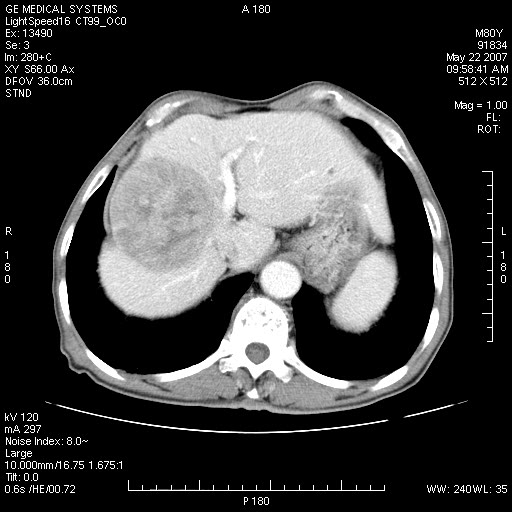

标题: CT8346:男,80岁。血尿,肝脏,膀胱占位,是否为肝转移?

男,80岁。血尿,无腹部不适病史。

膀胱病变:

增强原原发性肝癌、膀胱癌伴左侧盆腔淋巴转移。

肝脏内病灶有假包膜,增强扫描动脉期有动静脉瘘,有快进快出特点,考虑原发性肝癌。病灶内有裂隙样低密度影,以纤维板层样细胞癌可能性大。膀胱左侧乳头状占位,增强呈明显强化,左侧盆腔内有肿大淋巴结,结合有血尿病史,考虑膀胱癌左侧盆腔淋巴结转移。